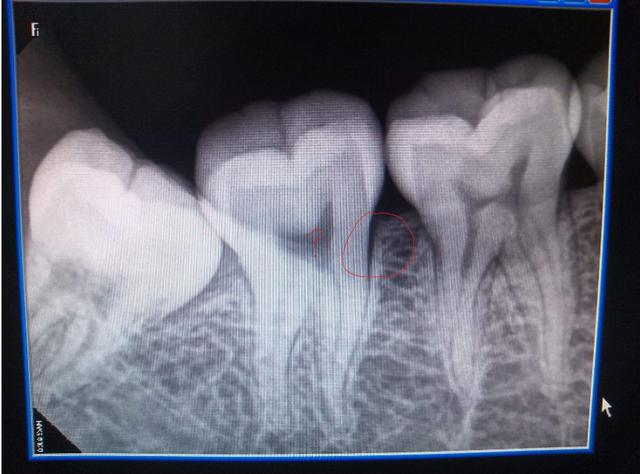

牙医还可能需要进行X射线检查,以检查智齿的排列并排除引起疼痛的其他可能原因,例如蛀牙。

牙医经常在临床评估过程中诊断冠周炎。 牙医将通过检查智齿并检查体征和冠周炎的外观来诊断病情。